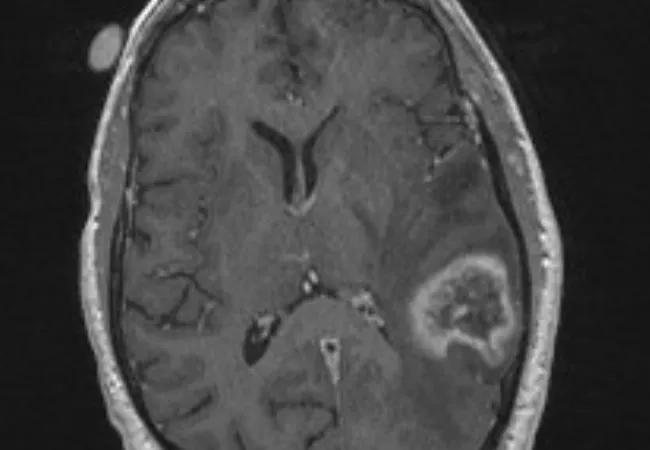

Preoperative (neoadjuvant) stereotactic radiosurgery (SRS) with dose escalation followed by surgical resection for brain metastases > 2 cm yielded local control comparable to that with postoperative SRS or whole-brain radiation therapy (WBRT) — with the benefits of acceptable acute toxicity and a low incidence of leptomeningeal disease.

For brain metastases larger than 2 cm, Dr. Murphy explains, single-session SRS alone results in local control of only about half the lesions, making surgery an important part of the therapeutic strategy. While WBRT following surgery is effective against recurrence, its use can be associated with significant acute and late toxicity, including a high rate of cognitive decline. Surgical resection followed by SRS to the resection cavity has its own disadvantages, including a significant risk that patients will develop leptomeningeal disease.

Preoperative SRS has been found to offer a number of advantages. Targeting metastases is technically easier before they have been removed, obviating the need to radiate a margin of normal tissue and thereby potentially reducing toxicity. Additionally, systemic chemotherapy can be started earlier, and the risks of leptomeningeal disease and cancer cell spillage may be lower because the tumor margin is “sterilized” preoperatively.